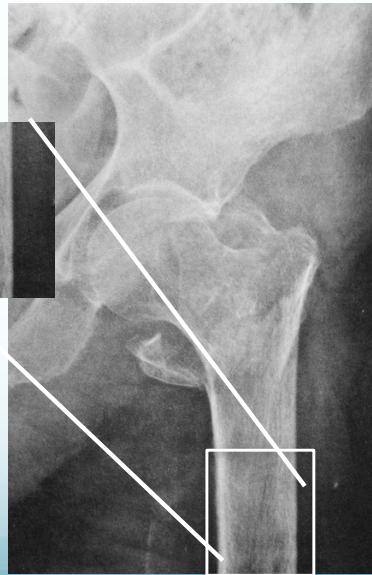

Common Fracture Sites ✓

- Neck of femur (has many complications)